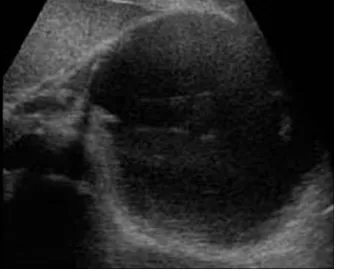

42세 여성이 10일 전부터 지속적인 복통과 38.5도의 발열을 호소하며 내원하였다. 환자는 2주 전에 심한 음주 후 급성 췌장염 진단을 받고 입원 치료를 받았었다. 아래는 복부 초음파 및 복부 CT 결과이다. 가장 적절한 치료 방법은 무엇인가?

[복부 초음파]

US, CT: 췌장 부위 경계가 명확한 cyst

Imp: 췌장 가성낭종 (pancreatic pseudocyst)

DDx: 구역성 췌장괴사(walled off necrosis, WON)

• 2주 전 급성 췌장염을 앓은 환자의 US, CT 상 췌장 부위 경계가 명확한 cyst가 관찰되므로 가성 낭종으로 진단 가능하다.

• WON은 경계가 불명확한 피막, heterogenous fluid, 낭종 내부 공기방울이 관찰되어 가성 낭종과 영상 소견 상 차이가 있다.